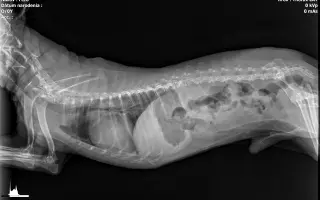

Fero absolvoval viacero základných aj rozšírených veterinárnych vyšetrení, ktoré potvrdili:

• pozitívne alergologické testy (roztoče, plesne – IDEXX),

• chronickú fibrotizáciu pľúc,

• výrazný kolaps trachey s paroxyzmálnym suchým kašľom,

• podozrenie na svrab, na ktorý liečba pravdepodobne zabrala.

Fero potrebuje trvalú medikáciu a liečba dýchacích ťažkostí bude, žiaľ, doživotná. Existuje aj možnosť chirurgického riešenia priedušnice, no zatiaľ veríme, že sa jej podarí vyhnúť.